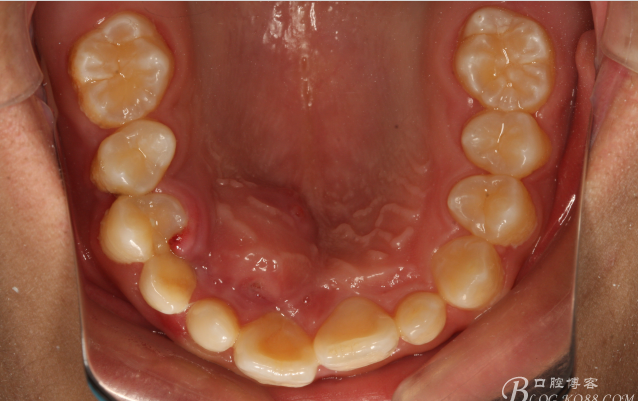

圖5.下頜開口位影像